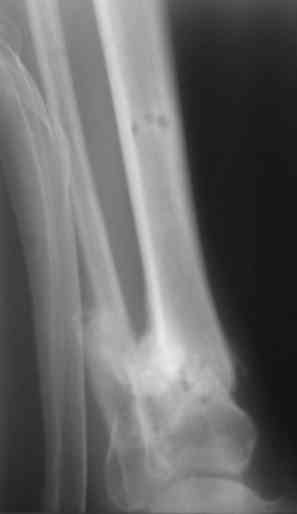

Re: Ведение огнестрельного перелома

Снимки очень интересны.

Но думаю, что самый лучший вариант - т.н. острое укорочение.

Тем более при относительно небольшой величине дефекта.

Есть у меня результат такого метода. Тема обсуждалась. Как говорится - лечили всем форумом. Рана, правда, не огнестрельная - OFFтопик.

Укорочение конечности 3 см. Передвигался без дополнительной опоры с "нарощенной" подошвой на правой обуви. Ограничение тыльного и подошвенного сгибания - умеренные (всего примерно 50%, не измерял).